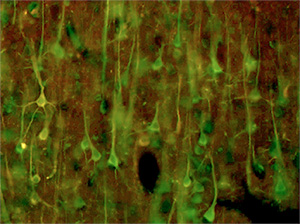

High pathology control 脳のMAP2 (Green) とCD59 (Red)の二重蛍光染色merge像。

細胞体が黄色のが、CD59 発現陽性の神経細胞。